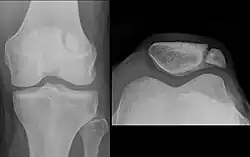

-

Transverse fracture of patella -

Comminuted fracture of patella -

Osteochondral fracture of patella -

Vertical patella fracture